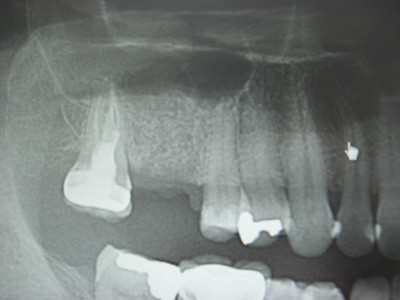

抜歯、ソケットプリザベーション、GBR

今日の午前中のオペは、歯根破折にて保存不可能な右上6番を抜歯し、(患者様は将来的にインプラントによる治療を希望されましたので)

同時にソケットプリザベーション、と側方へのGBR(骨造成)を施術いたしました。

CTにて精査しました所、根尖に歯根嚢胞も認められましたので、ピエゾにて完全に不良肉芽を掻破し、骨補填してオペ終了です。